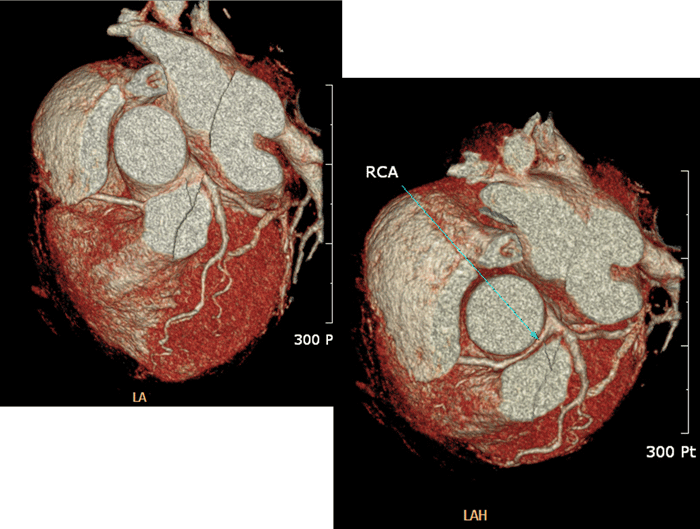

Heart 49 / F, Coronary CT angiography

Yeseul Jo, Jung Im Jung, Department of Radiology, Seoul St. Mary’s Hospital, the catholic university of Korea

HIT : 18